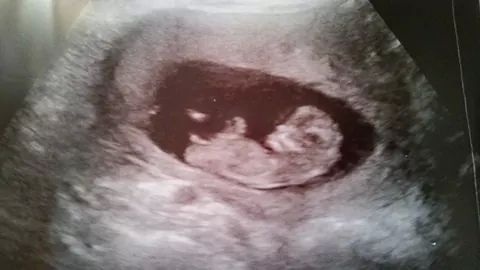

So I haven't been on here for ages but you ladies were helpful for me when I was swaying for pink and I got her!! I have a friend who just sent me this pic and wants to know my opinion. I know what I think, but I want to see what others think...... Please guess. I'm not sure how far along she is but I know it's +12wAttachment 22809